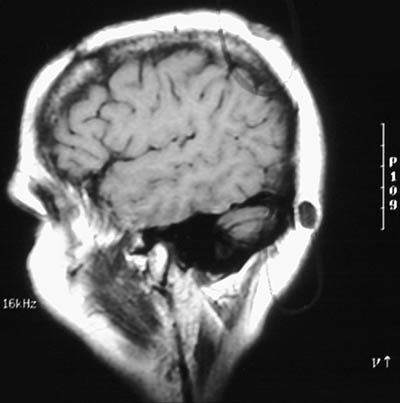

| The sagittal T1 weighted MRI scans of the head above and below reveal cysts in the scalp. The subcutaneous fat of the scalp is bright, while the acellular keratinaceous contents of the epidermal inclusion cysts are dark. A portion of epidermis trapped under the skin surface may continue to slowly grow and desquamate, producing the cyst. |